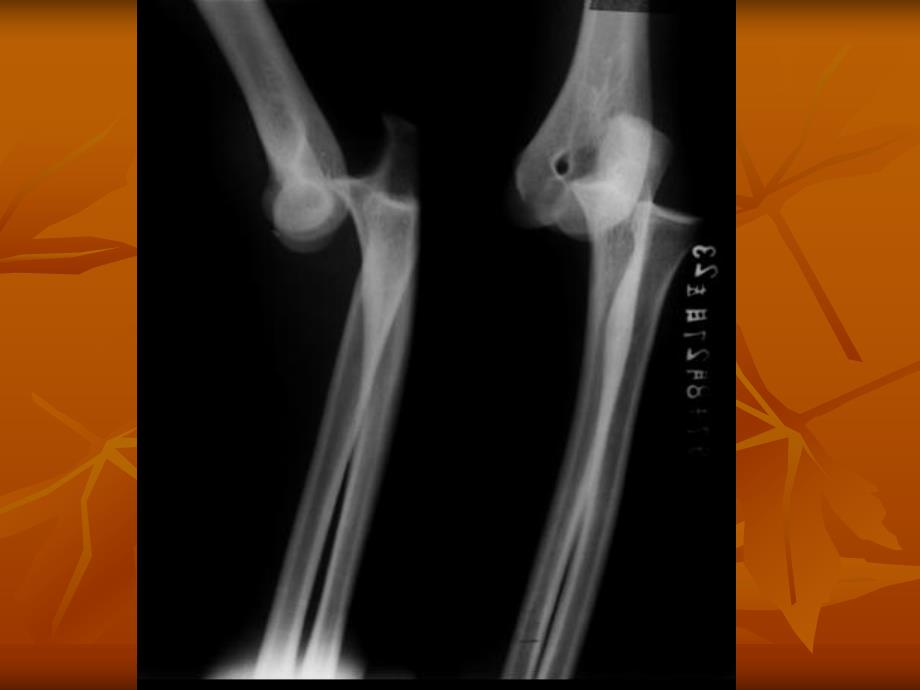

2、:肱骨内、外上髁及尺骨鹰嘴肘关节正位肘关节正位X线片线片肘关节侧位肘关节侧位X线片线片n2.肱动静脉n3.正中神经n4.桡动静脉n5.肱二头肌n6.肱二头肌腱肘三角肘三角病因病理病因病理n传达暴力n杠杆作用分类分类n后脱位n前脱位n外侧脱位(桡侧)n内侧脱位(尺侧)后脱位后脱位前脱位前脱位肘关节前脱位合并鹰嘴骨折肘关节前脱位合并鹰嘴骨折外侧脱位外侧脱位内侧脱位内侧脱位诊断要点诊断要点n外伤史n疼痛、肿胀、活动功能障碍肘关节后脱位肘关节后脱位n肘窝前饱满,可摸到肱骨下端。n尺骨鹰嘴后突,肘后空虚,成靴状畸型。n肘关节弹性固定在45度左右半屈位。n肘后三角关系改变。肘关节后脱位肘关节后脱位鉴别诊断

5、正常n屈伸活动是否恢复n肘后三角关系是否正常n桡骨头与肱骨外上髁的正常关系是否恢复nX线片肘关节正位肘关节正位X线片线片肘关节侧位肘关节侧位X线片线片固定方法固定方法n后脱位n 复位成功后,用三角巾悬吊前臂或肘后石膏托固定于屈肘90135度,或用8字绷带固定。n前脱位n 常合并鹰嘴骨折,按鹰嘴骨折处理,予伸直位石膏或屈肘15度石膏托固定.后脱位后脱位前脱位前脱位练功活动练功活动n 世医得效方n “不可放定,或时又用拽屈拽直。此处筋多,吃药后若不屈直,则恐成疾,日后屈直不得。”药物治疗药物治疗n 三期辩证n初期活血化瘀、消肿止痛n 外敷双柏散n中期合营生新、舒筋活络n 壮筋养血汤n后期补养气血n 八珍汤手术治疗手术治疗n 适应症n1.闭合复位失败者n2.肘关节脱位合并骨折,脱位复位后,骨折未能复位者。如合并肱骨内上髁骨折等。n3.陈旧性肘关节脱位,不宜试行闭合复位者n4.某些习惯性肘关节脱位。术式术式n切开复位术n肘关节成形术n肘关节融合术 小结(病例)小结(病例)n患者,男,22岁,工人。骑摩托车不慎跌倒,致左肘部肿痛,功能受限1小时来门诊治疗。n查体:肘前窝饱满,前后径增宽,肘后鹰嘴突异常后突,肘后上方空虚,肘后三角关系紊乱。肘关节后脱位肘关节后脱位肘后三角关系改变肘后三角关系改变n 诊 断?n 肘关节后脱位n 治 疗?n 手法复位